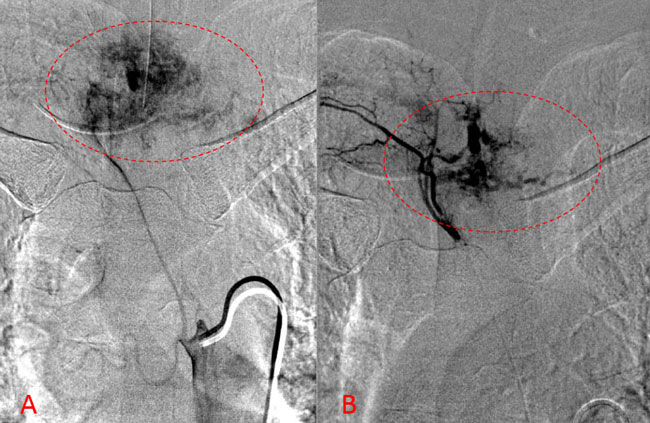

No spinal artery contributions were found to arise from this right T1-T3 pedicle. Superselective WADA testing was performed with Brevital injected through the microcatheter, which failed to elicit changes in the intraoperative monitoring, confirming safety to proceed with devascularization of this pedicle and tumor. This was performed with 100-300 micron particles achieving an excellent devascularization (Figure 3. A, B).

Figure 3. A and B) demonstrates selective PVA embolization with complete devascularization of the tumor on completed embolization.